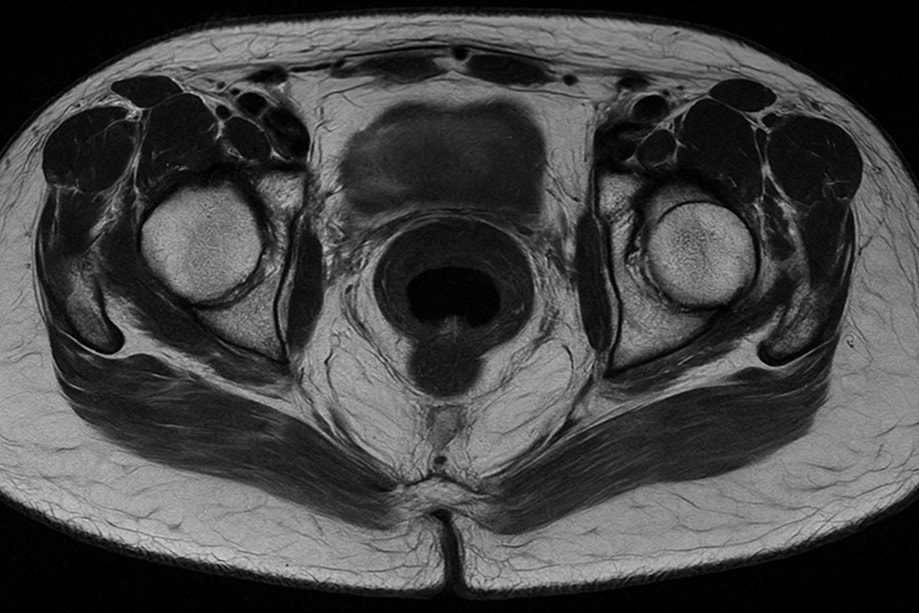

МРТ перианальной области позволяет получить высокоточные изображения мягких тканей и сосудистых структур в зоне анального канала. Методика помогает выявить воспалительные очаги, кисты, свищевые ходы, опухоли и оценить состояние мышц сфинктера.

Магнитно-резонансная томография перианальной области особенно информативна при диагностике хронических свищей и послеоперационных изменений. Она помогает врачу точно определить распространенность воспаления и выбрать оптимальную тактику лечения.

После сканирования врач оценивает снимки и готовит заключение. Магнитно-резонансная томография перианального пространства помогает определить размеры воспалительных полостей, наличие гнойных ходов, их протяженность и связь с соседними органами.

МРТ перианальной области с контрастом позволяет отличить злокачественные процессы от доброкачественных образований. Заключение включает описание тканей, степень поражения и рекомендации по дальнейшему лечению. При необходимости исследование можно сделать повторно для контроля динамики.